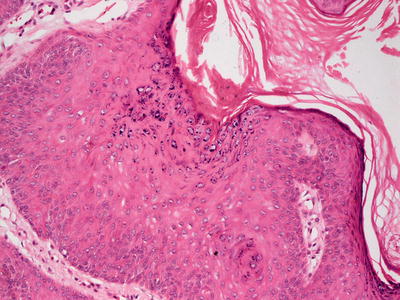

Early lesions demonstrate a moderate degree of epidermal acanthosis with significant pallor within keratinocytes at superficial levels of the epidermis (Figs. 12.7, 12.8 and 12.9). Within these cells, viral cytoplasmic inclusions are seen. Intraepidermal vesicles are often present secondary to marked edema within the dermis. The dermis demonstrates a proliferation of thin-walled vessels with a surrounding infiltrate of lymphocytes, histiocytes, and rare eosinophils and plasma cells [80, 81]. As the lesions evolve, epidermal necrosis is almost invariably present, often prominent in the central portions of the lesions. Neutrophils are present adjacent to the necrotic foci. Viral particles are readily apparent on electron microscopy [81].

Fig. 12.7

An acanthotic and spongiotic epidermis overlies a dense lymphohistiocytic inflammatory infiltrate in orf

Fig. 12.8

Prominent epidermal spongiosis and dense inflammation are seen in orf